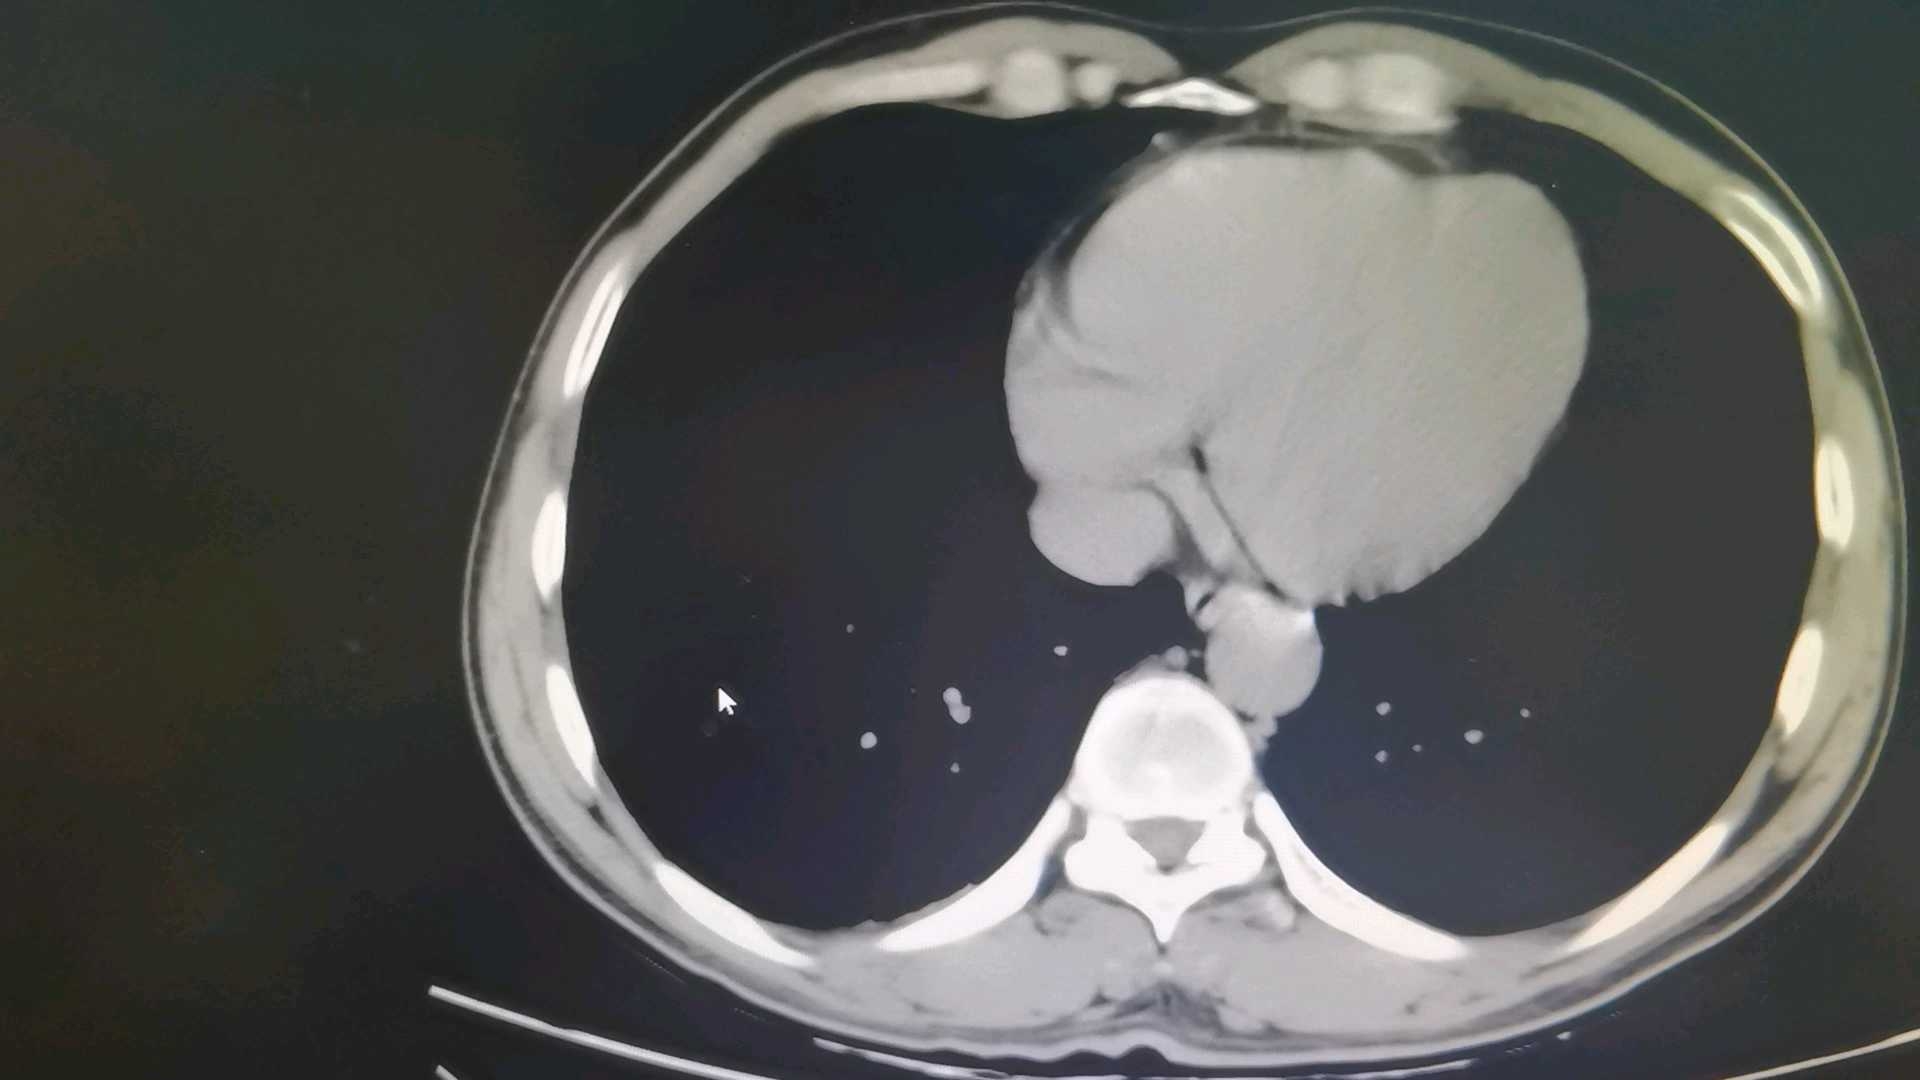

胰管结石并胰腺炎的治疗?

图片尺寸1920x1080